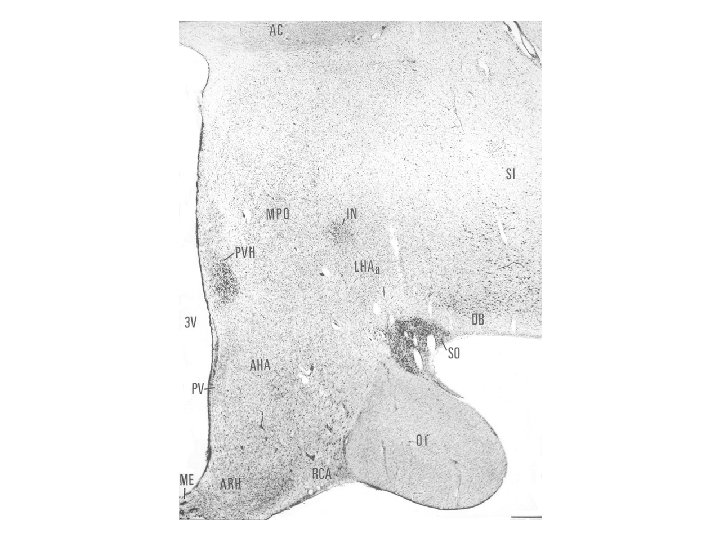

Nucleus arcuatus A hypothalamus magja a III. kamra alsó részének két oldalán, a retrochiasmaticus area és a corpus mamillare kezdete között, közvetlenül az eminentia medianától dorsolaterálisan. Sejtjeik számos neuropeptidet és peptid receptort, egy részük dopamint (A 12 catecholamin sejtcsoport) termel. Emberben nucleus infundibularisnak is nevezik. Neuronjai a hypothalamus más magjaihoz és a nyúltvelői és gerincvelői autonóm sejtekhez projíciálnak. A mag mediális részében nincs vér-agy gát. Jelentős szerepet visz a táplálékfelvétel idegrendszeri szabályozásában.

Nucleus dorsomedialis hypothalami A hypothalamus középső részében, a harmadik agykamra két oldalán, a nucleus ventromedialis felett helyezkedik el. Neuronjai több szubdivíziót alkotnak, melyek a táplálékfelvétel központi szabályozásában és a stressz válaszban visznek szerepet.

Hypothalamus szerepe a só- és vízháztartás szabályozásában A vasopressin a magnocellularis paraventricularis és supraopticus magokban termelődik. A vasopressint korábban antidiureticus hormonként (ADH) írták le, és ez az elnevezés ma is használatos a klinikumban. A vasopressin szintézisében és a neurohypophysisbe juttatásában, illetve az onnan történő felszabadításában két másik hormon az angiotensin II, és atrialis natriureticus hormon visz szerepet. Az előző a vesében termelődő renin-angiotensin rendszer aktív tagja, mely a vér-agy-gát-mentes subfornicalis szerven keresztül jut be az agyba, míg az utóbbit a preopticus area neuronjai termelik.

Nucleus paraventricularis hypothalami A hypothalamus egyik legjelentősebb magja, magno- és parvocellularis részre osztható. A magnocelluláris neuroszekretoros sejtek vasopressint és oxytocint termelnek, axonjaik a tractus hypothalamo-hypophysealis egy részét alkotják, és a hypothalamus hátulsó lebenyében végződnek. A parvocelluláris neuroszekretoros idegsejtek több peptiderg neurohormont (corticotropin-releasing hormon – CRH, thyrotropin-releasing hormon – TRH, vasopressin) és neuromodulátort (neuropeptidet) termelnek. A parvocellularis neuronok egy része az eminentia mediana portális erei révén juttatja el termékét a hypophysis elülső lebenyébe, másik részük a nyúltvelőbe és a gerincvelőbe projíciál. A CRH-termelő idegsejtek révén a paraventriculáris magot a stresszválasz központi részének, a „hypothalamohypophysis-mellékvesekéreg szabályozó rendszer” („HPA axis”) kiinduló pontjának tekintik.